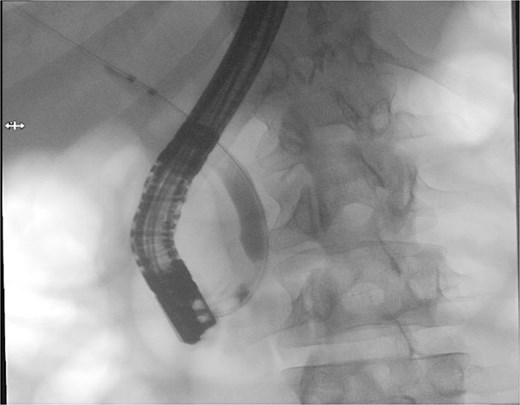

Patient subsequently performed endoscopic retrograde cholangiopancreatography with needle-knife cannulation. Cholangiogram confirmed a distal CBD filling defect. A sphincterotomy and balloon sweep were performed, successfully extracting stones, and an 8.5 Fr × 7 cm stent was deployed (Fig. 3, Fig. 4).

Therapeutic ERCP fluoroscopic image demonstrating successful biliary sphincterotomy, balloon stone extraction, and placement of a biliary stent within the common bile duct.